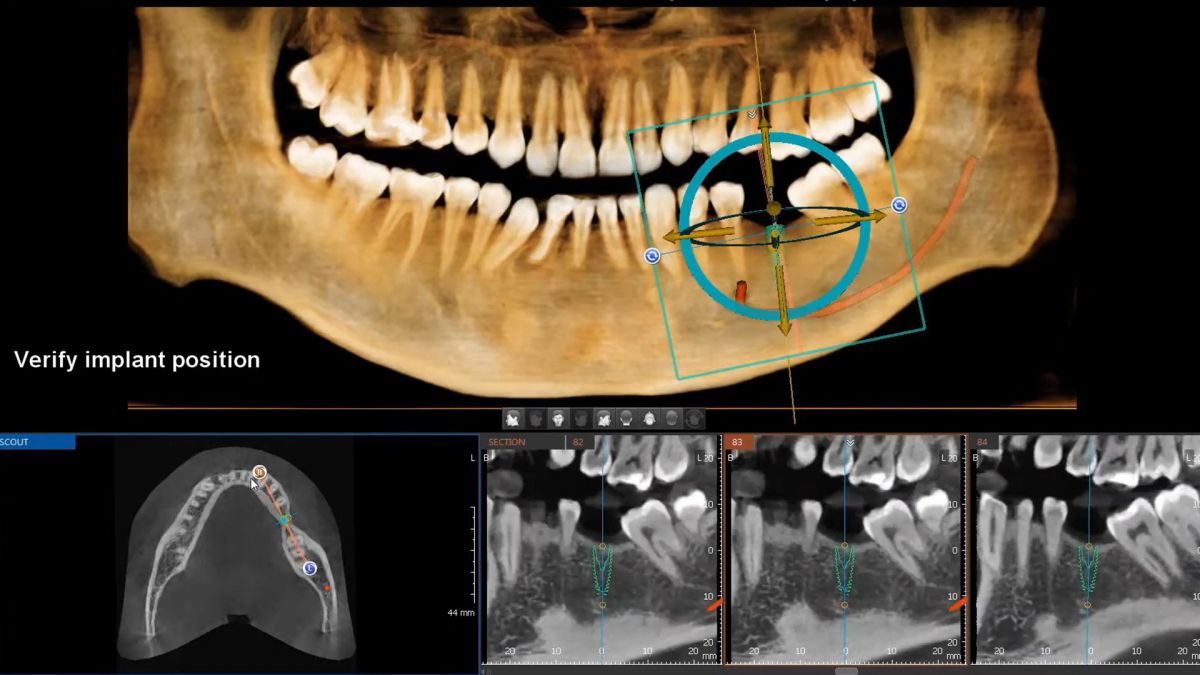

+ Hansmart – Lên kế hoạch điều trị an toàn, duy trì kết quả dài lâu: Dữ liệu từ CT cone beam và dữ liệu scan mẫu hàm kỹ thuật số được tích hợp vào Hansmart giúp bác sĩ tầm soát cấu trúc xương hàm, mạch máu, dây thần kinh, khảo sát mật độ xương chất lượng xương, cấu trúc vi tế từ đó lựa chọn vị trí đặt implant an toàn, tính toán độ sâu, góc nghiêng và cân bằng theo ba chiều không gian giúp răng sứ được phục hình chuẩn khớp cắn khôi phục chức năng thẩm mỹ và ăn nhai giúp răng implant chịu lực tốt, duy trì kết quả dài lâu.